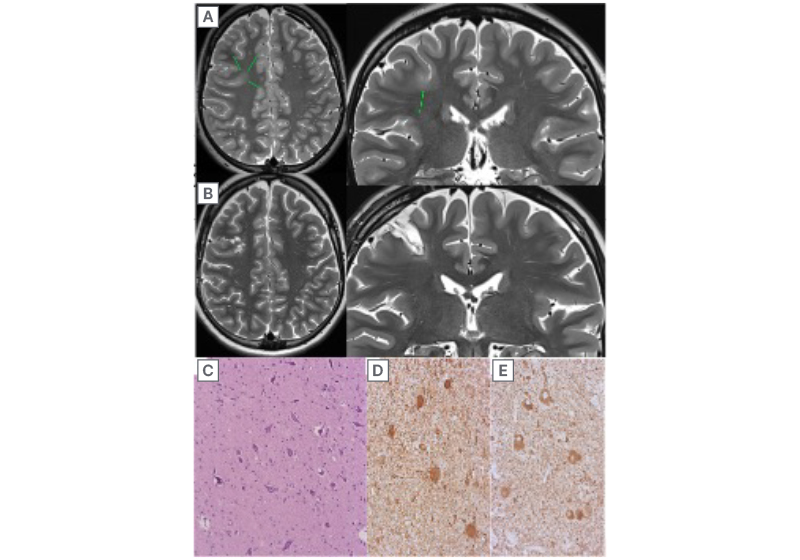

Figure 1: Focal cortical dysplasia Type IIb of the right frontal lobe.

Condition before surgery (A) and after surgery (B). The transmantle symptom was not visualised before surgery. The data were confirmed histologically (C) and immunohistochemically (D, E). C) Accumulation of pathological forms of neurons surrounded by fibrous gliosis, staining with haematoxylin and eosin. D) Balloon cells, vim expression. E) Dysmorphic neurons, expression of neurofilaments.7